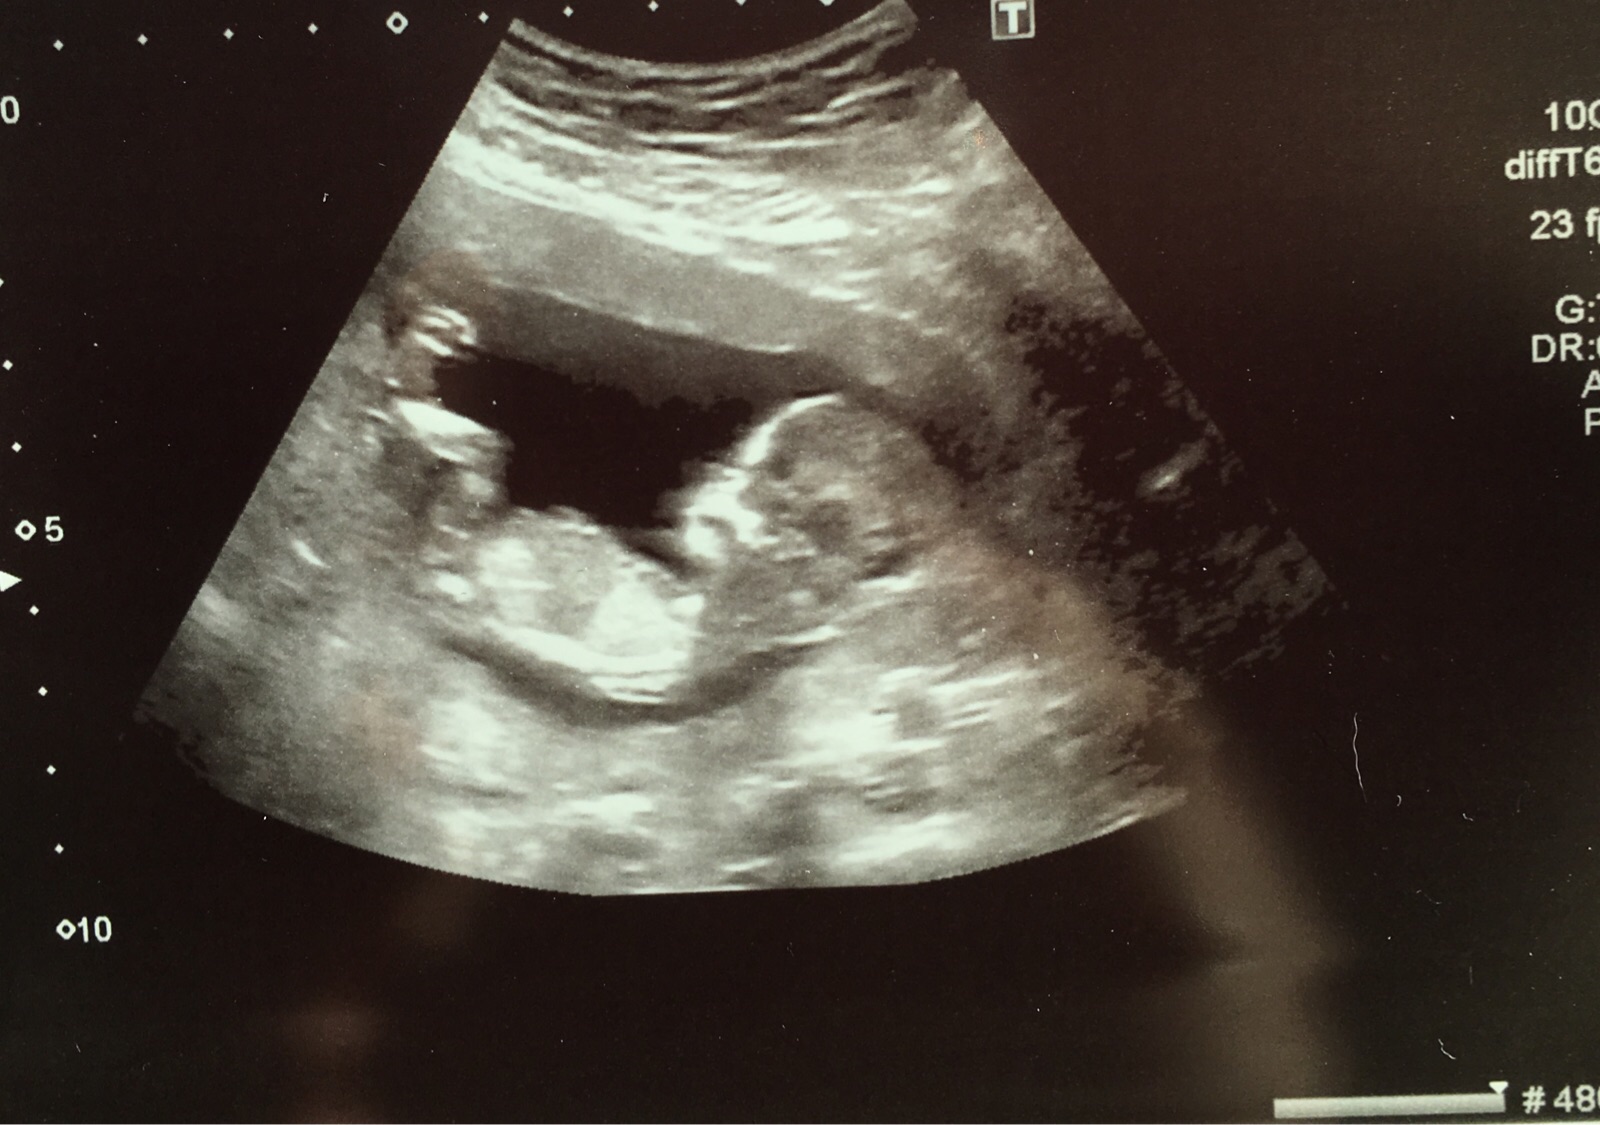

Attachment 27738Attachment 27740I understand there's no nub showing but I would love some predictions. Baby looks very different to my boy scans, but having said that I still look at it and think boy. Thank you!